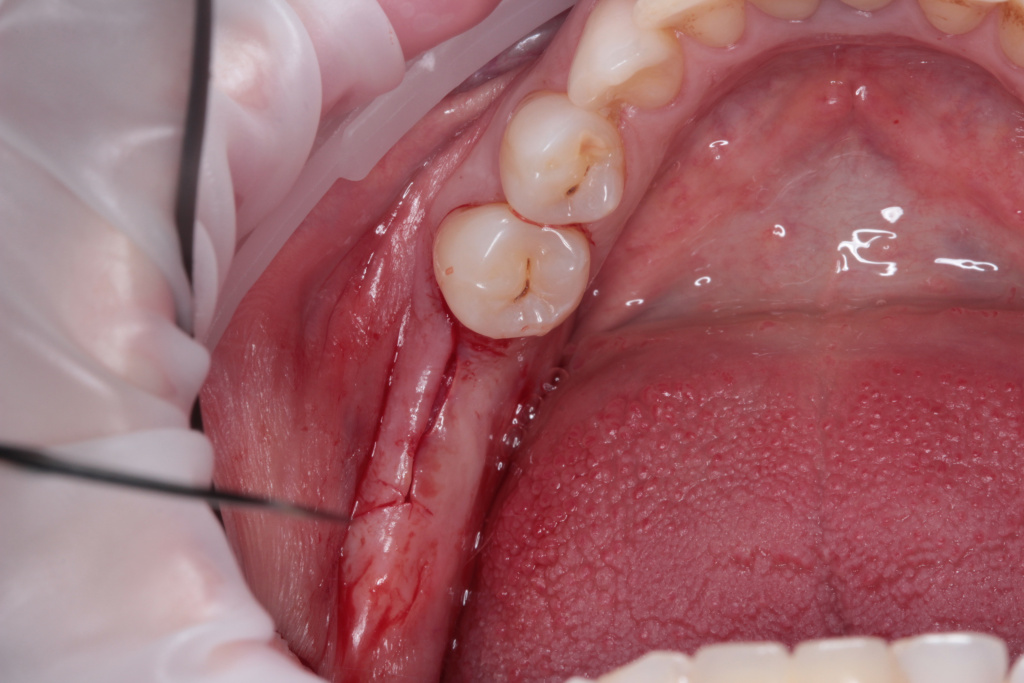

- Атравматичное удаление

- Пластика десны